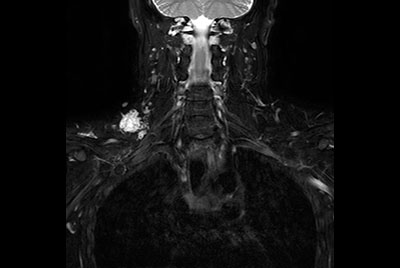

Brachial plexus tumor

Brachial Plexus with a hemangioma

Brachial Plexus lesion

Non-invasive nerve plexus imaging